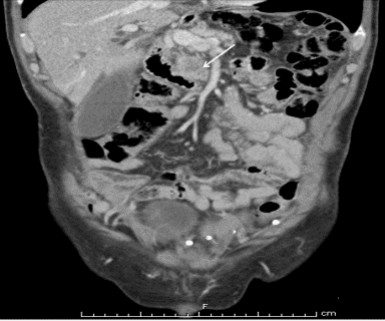

Evaluation with an abdominal ultrasound showed a questionable mass in the head of the pancreas. A CT scan revealed a 2.9 cm soft tissue mass in the head of the pancreas and uncinate process with associated pancreatic ductal and adjacent biliary ductal dilatation (Figure 2). A Whipple procedure was performed and pathology was consistent with a poorly differentiated exocrine adenocarcinoma of the pancreatic head (Figure 3) with invasion into the common bile duct and metastases to two of eight peripancreatic lymph nodes (stage T3N1M0). The patient underwent adjuvant radiation therapy along with capecitabine followed by weekly gemcitabine, with a plan to complete a total of six months of adjuvant chemotherapy. However, a restaging CT of the abdomen and pelvis two months later showed studding along the greater omentum and mesentery, which was concerning for early peritoneal spread of the tumor. A PET/CT revealed intensely increased metabolic activity in the gallbladder fossa measuring 5.8x3.4 cm with a maximum standardized uptake value (SUVm) of 10.3. There was an additional focus of intensely increased metabolic uptake near the left anterior abdominal wall with a maximum SUVm of 5.8. Due to obvious metastatic disease, he was started on systemic chemotherapy with folinic acid (leucovorin), 5-fluorouracil, irinotecan and oxaliplatin (FOLFIRINOX). Two months later, a restaging PET/CT showed a new 3 cm metastasis in the right lobe of the liver. The patient’s condition deteriorated rapidly; he developed sepsis secondary to cholangitis and was admitted to the intensive care unit. A family decision was ultimately made to focus on comfort-oriented care, and he expired soon thereafter.

Figure 2. Abdominal CT scan showing a low-attenuation mass (arrow) in the head of the pancreas and uncinate process, consistent with pancreatic adenocarcinoma. |